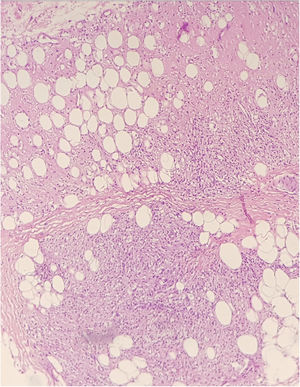

The histopathological examination of the biopsies performed at two sites showed an extensive dermal infiltrate predominantly consisting of interstitial, superficial and deep foamy macrophages, full of bacilli, forming globia, in addition to neutrophils around and inside the vessel walls and presence of bacilli in the vessel lumen, leukocytoclasia and extravasation of red blood cells, characterizing leukocytoclastic vasculitis, compatible with LP (Figs. 4 and 5)